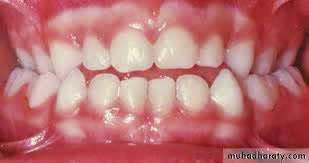

4/ Những dấu hiệu phụ huynh cần lưu ý

Nếu bé có các biểu hiện sau, cha mẹ nên đưa trẻ đi khám sớm:

- Khớp cắn ngược (răng dưới chìa ra trước)

- Khớp cắn hở (khi cắn lại vẫn hở khe giữa răng trước)

- Hàm hẹp, răng mọc chen chúc rõ rệt

Nguồn: Myfaceology

Nguồn: sarkissiandds

Nguồn: kidsdentalonline